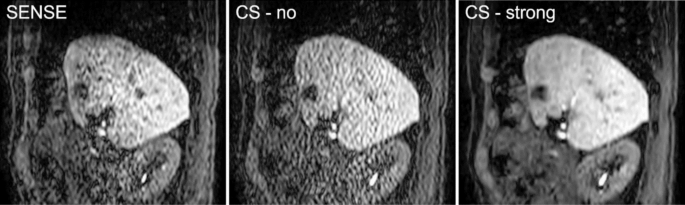

For qualitative analysis, lesion conspicuity, contrast enhancement, image noise, motion smoothness, and overall image quality were evaluated and scored by two radiologists (16 and 21 years of experience) on a 4-point scale (excellent, 4; good, 3; poor, 2; non-diagnosis, 1) in consensus under the three conditions (Fig. 8).

Representative cine-magnetic resonance imaging images with SENSE, CS-no, and CS-strong. Image artifact caused by parallel imaging is evident in the center of the image with SENSE. Mild image artifact is distributed through the whole range of the image with CS-no, whereas the artifact is reduced in the image with CS-strong. SENSE, sensitivity encoding; CS, compressed SENSE.